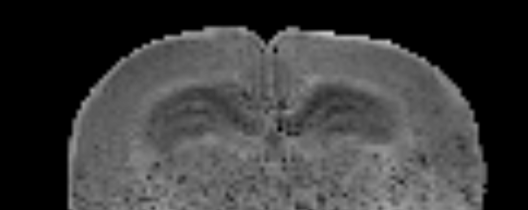

Mapas de métricas MDE. Este análisis está basando en el modelo del DTD.

\( C_{MD} \) Cuantifica la varianza de difusividad media (tamaños de tensores)

\( C_{c} \) Cuantifica la dispersión (coherencia de direcciones) de los tensores

\( C_{M} \) Cuantifica la anisotropía promedio (relacionada a FA en DTI)

\( C_{\mu} \) Cuantifica la anisotropía microscópica promedio (formas de los tensores)

Mayor info de estas métricas en link